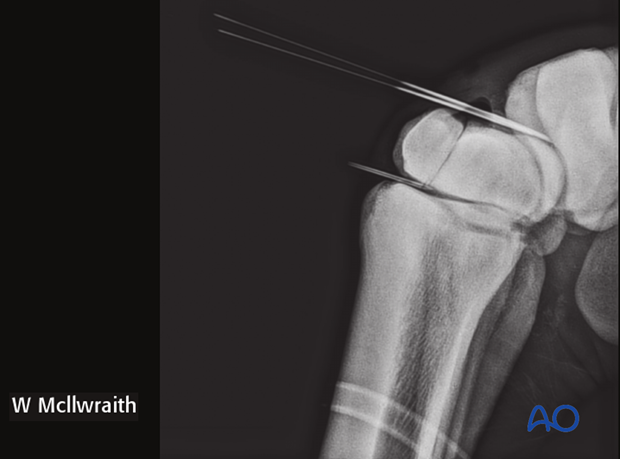

The proximal medial and lateral margins of the fracture are defined by arthroscopically guided percutaneous insertion of 18 gauge hypodermic needles.

It is important that these needles are placed perpendicular to the dorsal surface of the carpus in order to accurately delineate the fracture width.

Two 18 gauge spinal needles are then placed over the central portion of the radial and intermediate facets of the third carpal bone. These two needles are close and parallel to the proximal articular surface and directed approximately perpendicular to the fracture line. These needles are critical guides for implant placement. Once the spinal needles have been placed, the lateral and medial hypodermic needles are removed.

A flexed LM and ...

…skyline radiographic views are taken to provide the proximal-distal location of the lag screw.

Based on the radiographs two stab incisions are placed over the dorsal aspect of the radial and the intermediate facets respectively. Their positioning is based on radiographs of spinal needle placement.